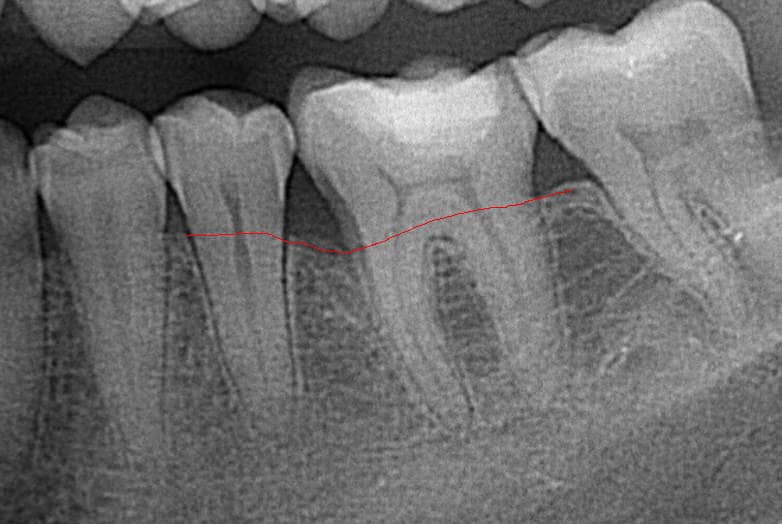

A következő képen pedig a regeneratív műtét után 6 hónappal később az elért csont visszaépülése látható.